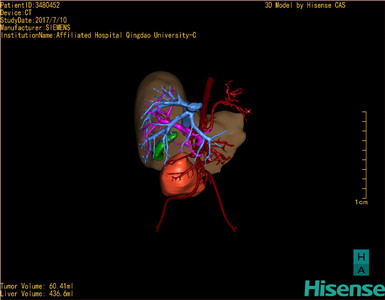

通过调节窗宽窗位调整CT序号,对肿瘤,肝实质,胆囊,下腔静脉,肿瘤,肝动脉、门静脉及肝静脉等进行三维重建;系统自动计算肿瘤体积和肝脏体积。模拟手术操作,自动计算切除肿瘤体积。肝脏体积为436.6ml,肿瘤体积为60.41ml,与血管联系紧密,术前手术方案的规划。

术前三维重建:

重建图片